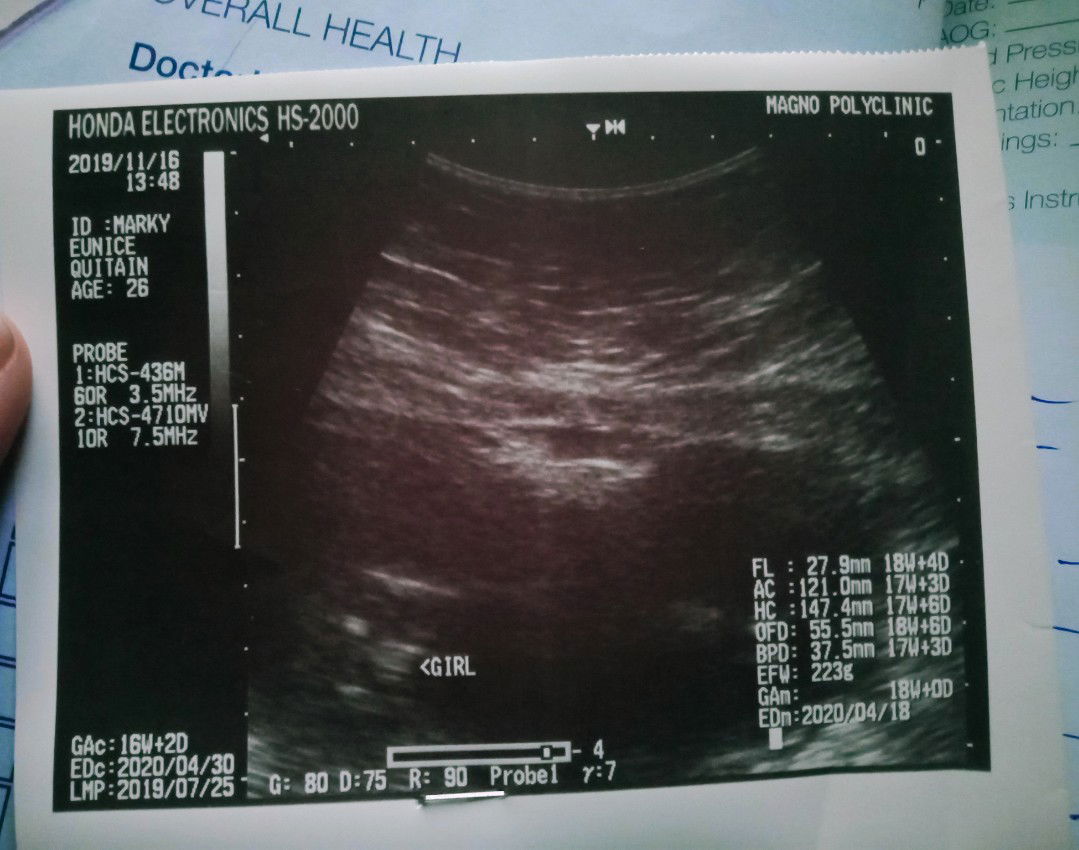

Gender reveal. ???

Ten little fingers, ten little toes Two little eyes, one little nose One little mouth, two little ears This poem will be lots of cheers So is it pink or is it blue We think it's time that you all knew The doctor searched while baby turned With her next three words here's what we learned! She told us then, that she thinks We need to start buying lots of PiNK! ????β?β? I love you so much, little version of me! ? 80% baby girl! ?? 18 weeks. ?